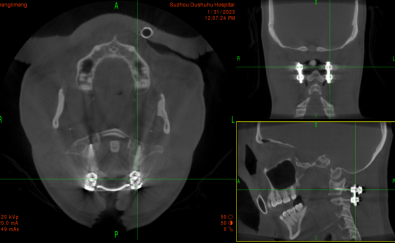

术中“O”-臂机导航图像

在麻醉手术科的配合下,有了高精尖的第二代“O”-臂机的辅助,加之姜主任丰富的临床经验,手术非常顺利。第二代“O”-臂机扫描颈椎三维重建显示寰椎移位的骨块复位完成,寰枢椎椎弓根螺钉位置良好。术后,患者颈部疼痛症状明显改善。